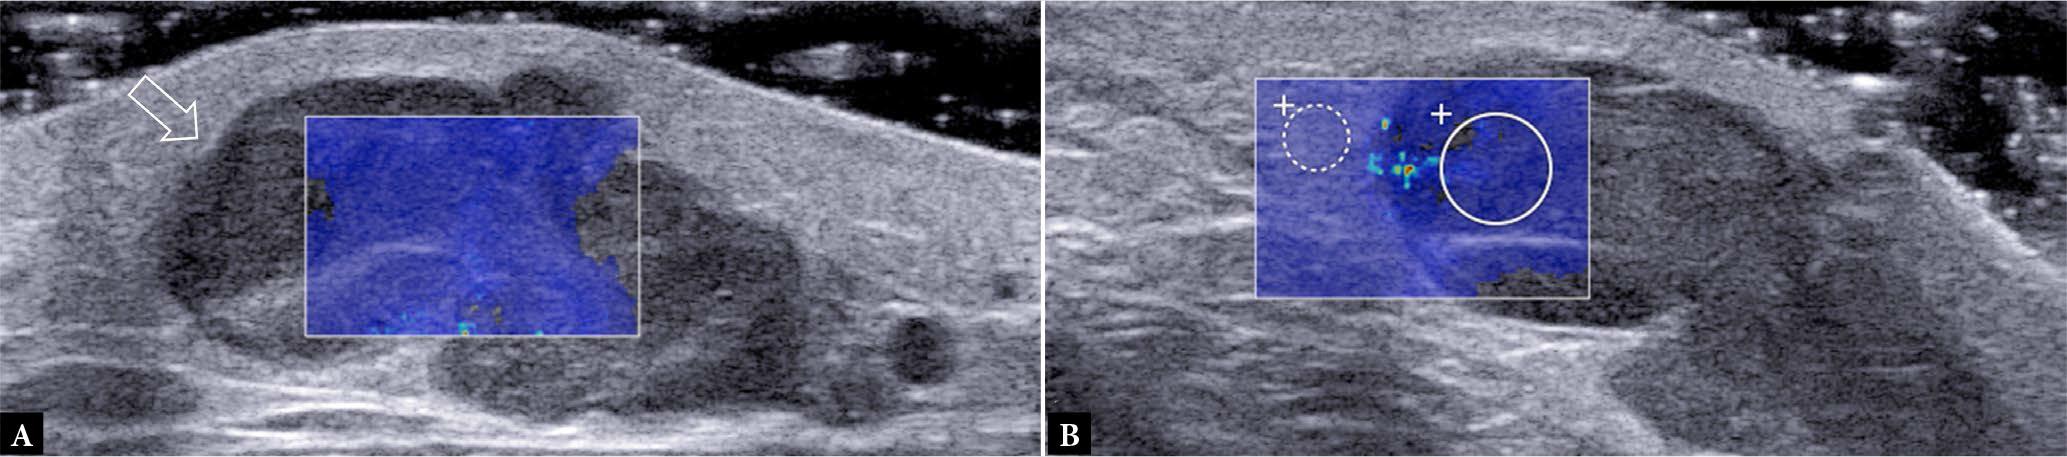

Fig. 1.

63-year-old male with enlarging thigh mass for five months. Transverse A. greyscale and B. color Doppler ultrasound show large moderately hyperemic mass (arrows) partially encasing the femoral (F) cortex. The large size, rapid growth, and moderate hyperemia make sarcoma most likely. No necrosis is evident. C. Axial proton-density weighted image shows that the tumor contacts, but does not infiltrate, the femoral cortex. The femoral neurovascular bundle (NVB) is also not infiltrated (arrowhead). T1-weighed fat-saturated post-contrast D. axial and E. sagittal images show that the central tumor area (*) is non-enhancing, compatible with necrosis. The necrosis cannot be appreciated on ultrasound A., B. Percutaneous biopsy of the tumor margins revealed a pleomorphic rhabdomyosarcoma